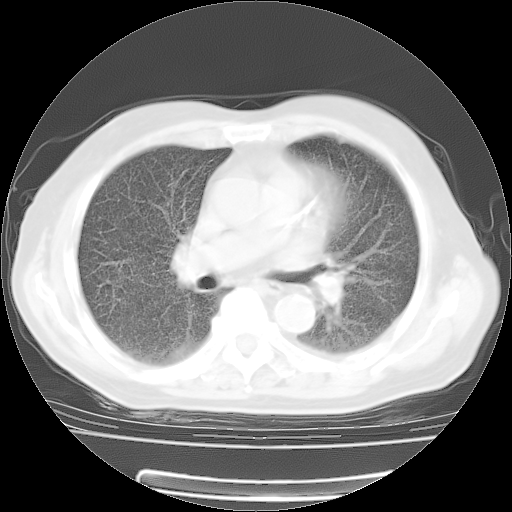

4月14日肺部CT